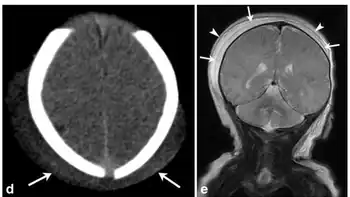

d)Axial CT image in a male infant with history of traumatic delivery demonstrate scalp soft tissue overlying bilateral parietal regions and crossing the sagittal suture e) demonstrates a deep subaponeurotic scalp fluid collection crossing the sagittal suture and extending anteriorly into the right temporal region, consistent with subgaleal hematoma, superficial overlying fluid collection with a similar distribution also noted; collection is within the subcutaneous fibrofatty tissues superficial to galea aponeurosis and is consistent with caput succedaneum